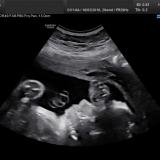

Auguri Yolanda.gordon, anche noi finito la morfologica che io mi sono commossa tantissimo xche nn me lo aspettavo ad vederla in 3d,e bellissima,ed pesa 400 gr ed è lunga 21 cm,tutto procede benissimo,grazie a Dio :heart:  :heart: ,come periodo e perfetto infatti la dpp e il 4 dicembre  :yahoo:  :yahoo: abbiamo superato anche questo …mi ricordo come fosse ieri il giorno in cui ho fatto il test è ora siamo a metà strada  :yahoo:  :yahoo:  :yahoo:  :yahoo: e un emozione umica ,un bacio a tutte

Noi visita finita.. Il gine era propenso a farmi foto 3 d ma la piccola no! Era con la faccia completamente schiacciata contro la mia schiena… E sempre.carponi e a testa in giù! Vai a vedere che il giorno fatidico si fa trovare podalica!!! Pesa 383 g e ora prossima visita 15 settembre.. Anche se devo andare in ospedale a fare un ecocardiografia visto che la morfo l’ho fatta troppo presto e questo esame nn si è potuto vedere bene..

Riccardo pesa circa 330 grammi, dovrebbe misurare tra i 18 e i 20 cm… la gine gli ha fatto un sacco di foto e misurazioni, anche al pisellino! E una Foto 3D della faccina  :heart:

Ciao a tutte e’ un po’ di tempo che non scrivo ma vi leggo sempre…..questa mattina morfologica andate bene Samuele pesa 340 grammi ed e’ 21 cm…..questo esame mi fa’sempre emozionare…..un abbraccio a tutte